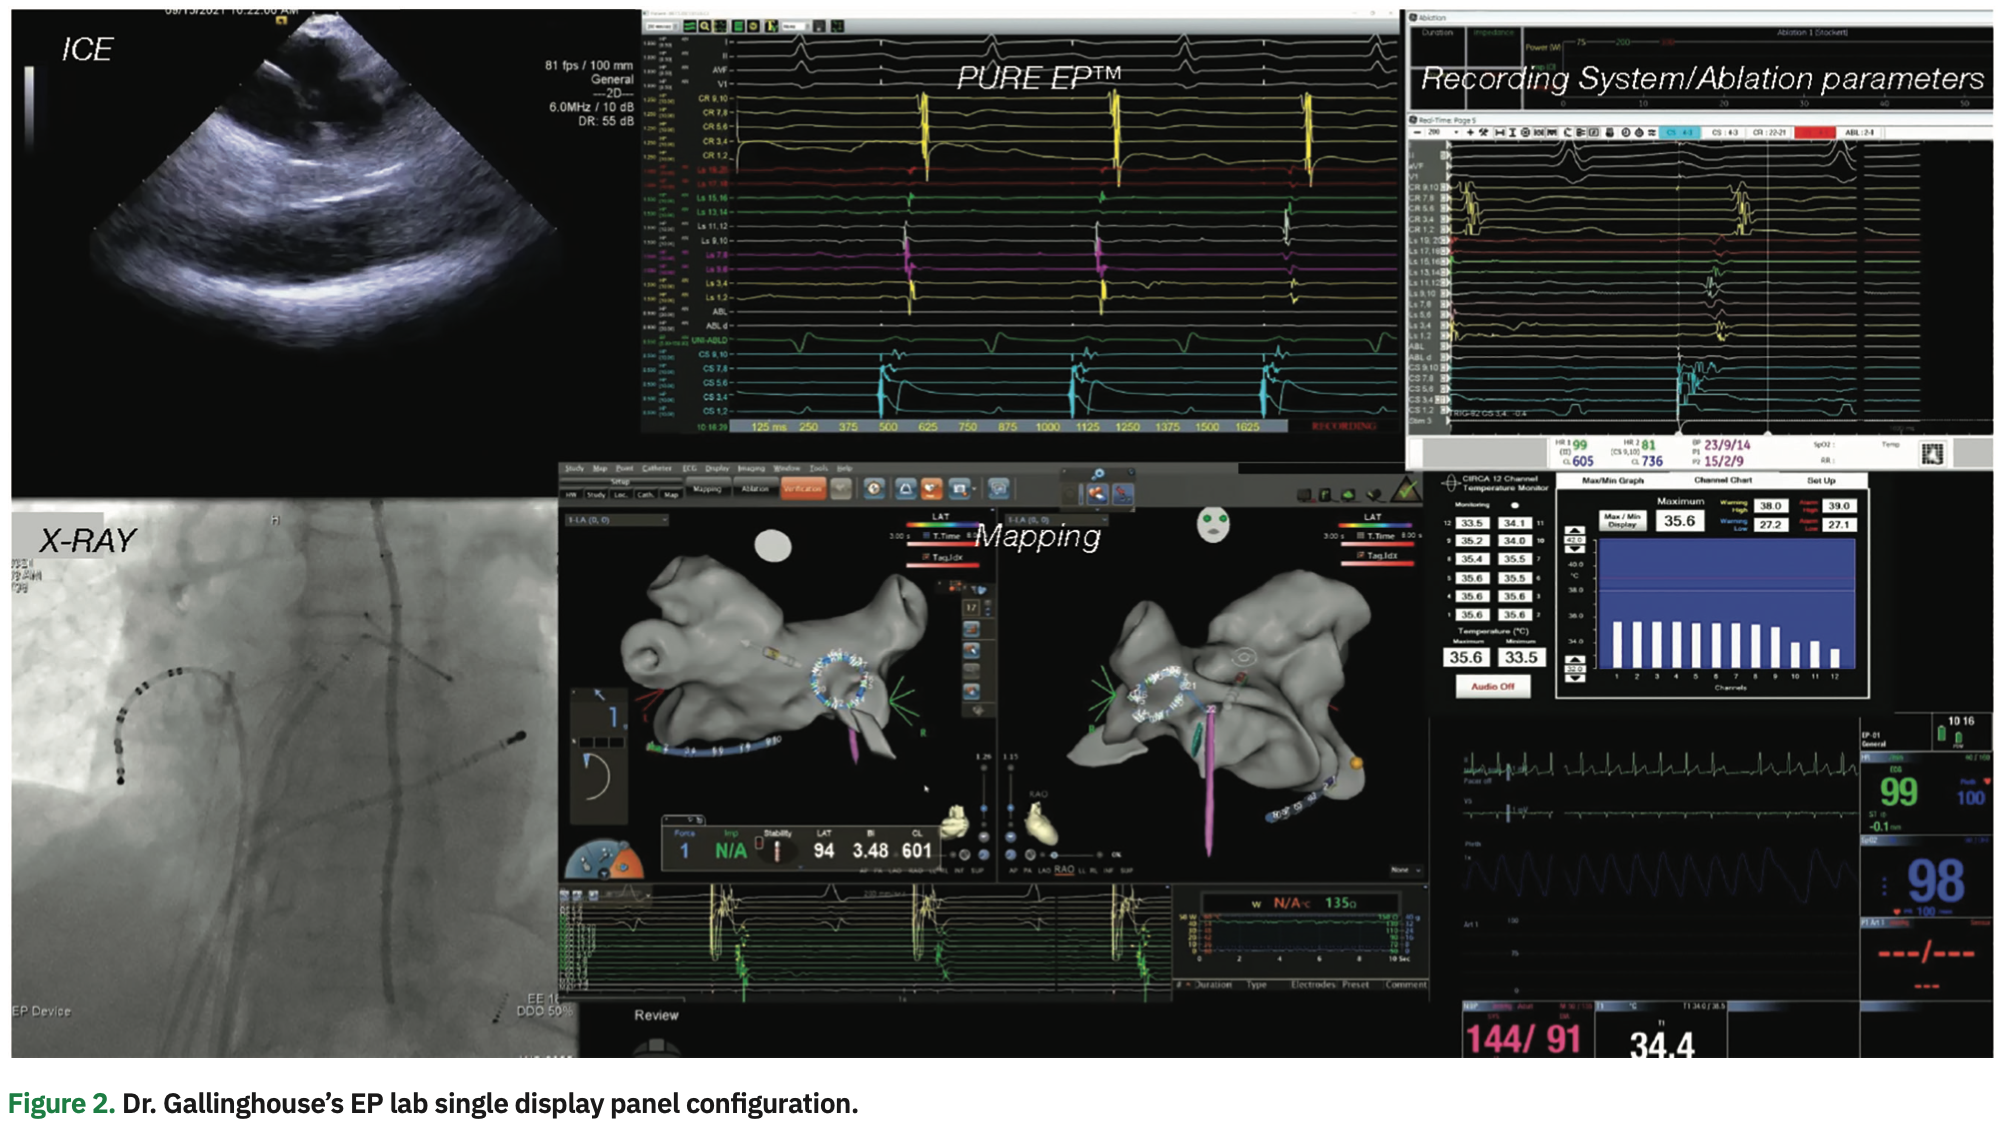

Now that you’ve been using the PURE EP™ technology for about two years, how do you incorporate the improved signal information into your clinical workflow?

We’ve made PURE EP™ signals central to our workflow, and it has become the primary source of physiologic signal information. For our setup, we have visualization of two screens: the PURE EP Live window and the 3D mapping window. Since it is essential to clearly discern small, fractionated signal potentials to effectively treat complex arrhythmia substrates, the focus is on the PURE EP window. We enhance the 3D map by tagging small, fractionated signals seen on PURE EP™, which we consider critical to the case. Overall, PURE EP™ enhances our interpretation of the 3D map and allows more precise treatment of ablation targets.